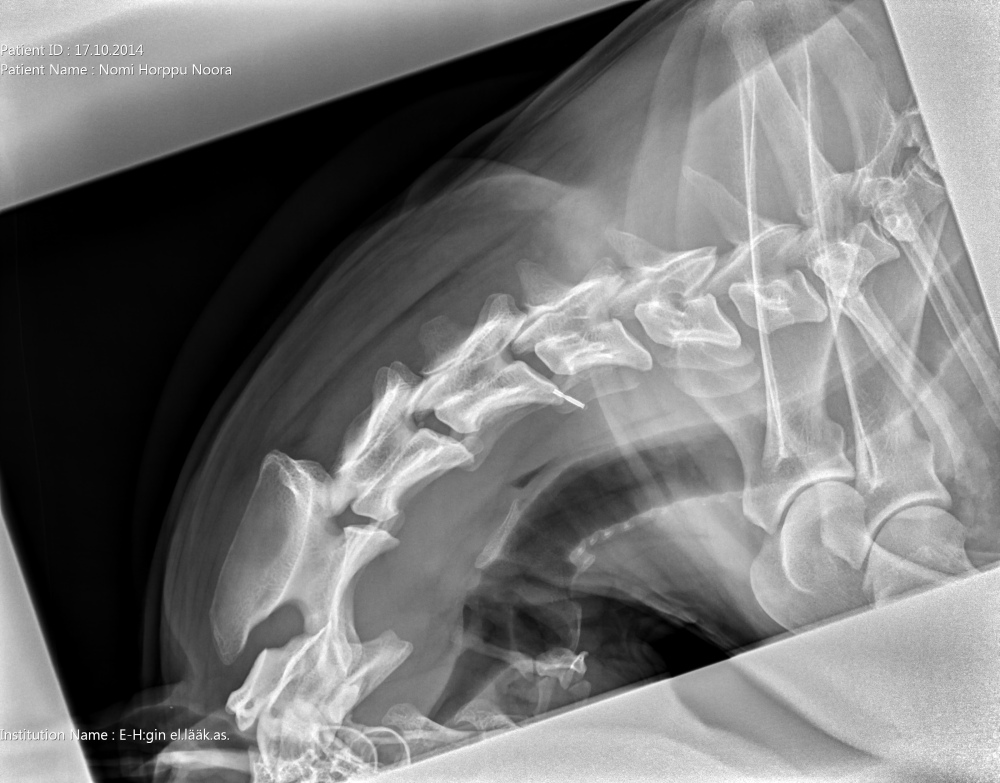

Niskasta otettu taivutuskuvat 17.10.14:

kaularanka1

kaularanka2

kaularanka3

Quti viety lääkäriin, koska vingahtelee kääntäessän päätään. Koko selkä kuvattiin, ei muutoksia. Oireiden jatkuessa kaularanka

magneettikuvattiin. Kuvanneen eläinlääkärin mielestä Nomilla on välilevyrappeuma ja kaikki harrastaminen mietittävä uudelleen.

Halusimme toisen mielipiteen Timo Talviolta, joka halusi ottaa Nomin kaularangasta taivutuskuvat. Talvion mukaan kyseessä ei ole

välilevyrappeuma vaan taivutuskuvissa näkyy kaularangan nikamien 5 ja 6 välillä liukuma. Lääkekuurin ja levon jälkeen voi

harrastamista jatkaa normaalisti. Talvion lausunto:"Kyse on nikamien välisestä "löysyydestä". Selkärangan rakenteelliset

viat ovat pääsäänöisesti perinnöllisiä, mutta tällainen lievä nikamien välinen liikkuvuus ei sellaisenaan ole perinnöllistä,

toki perintötekijät voivat altistaa tämänkaltaisen tilan kehittymiseen."